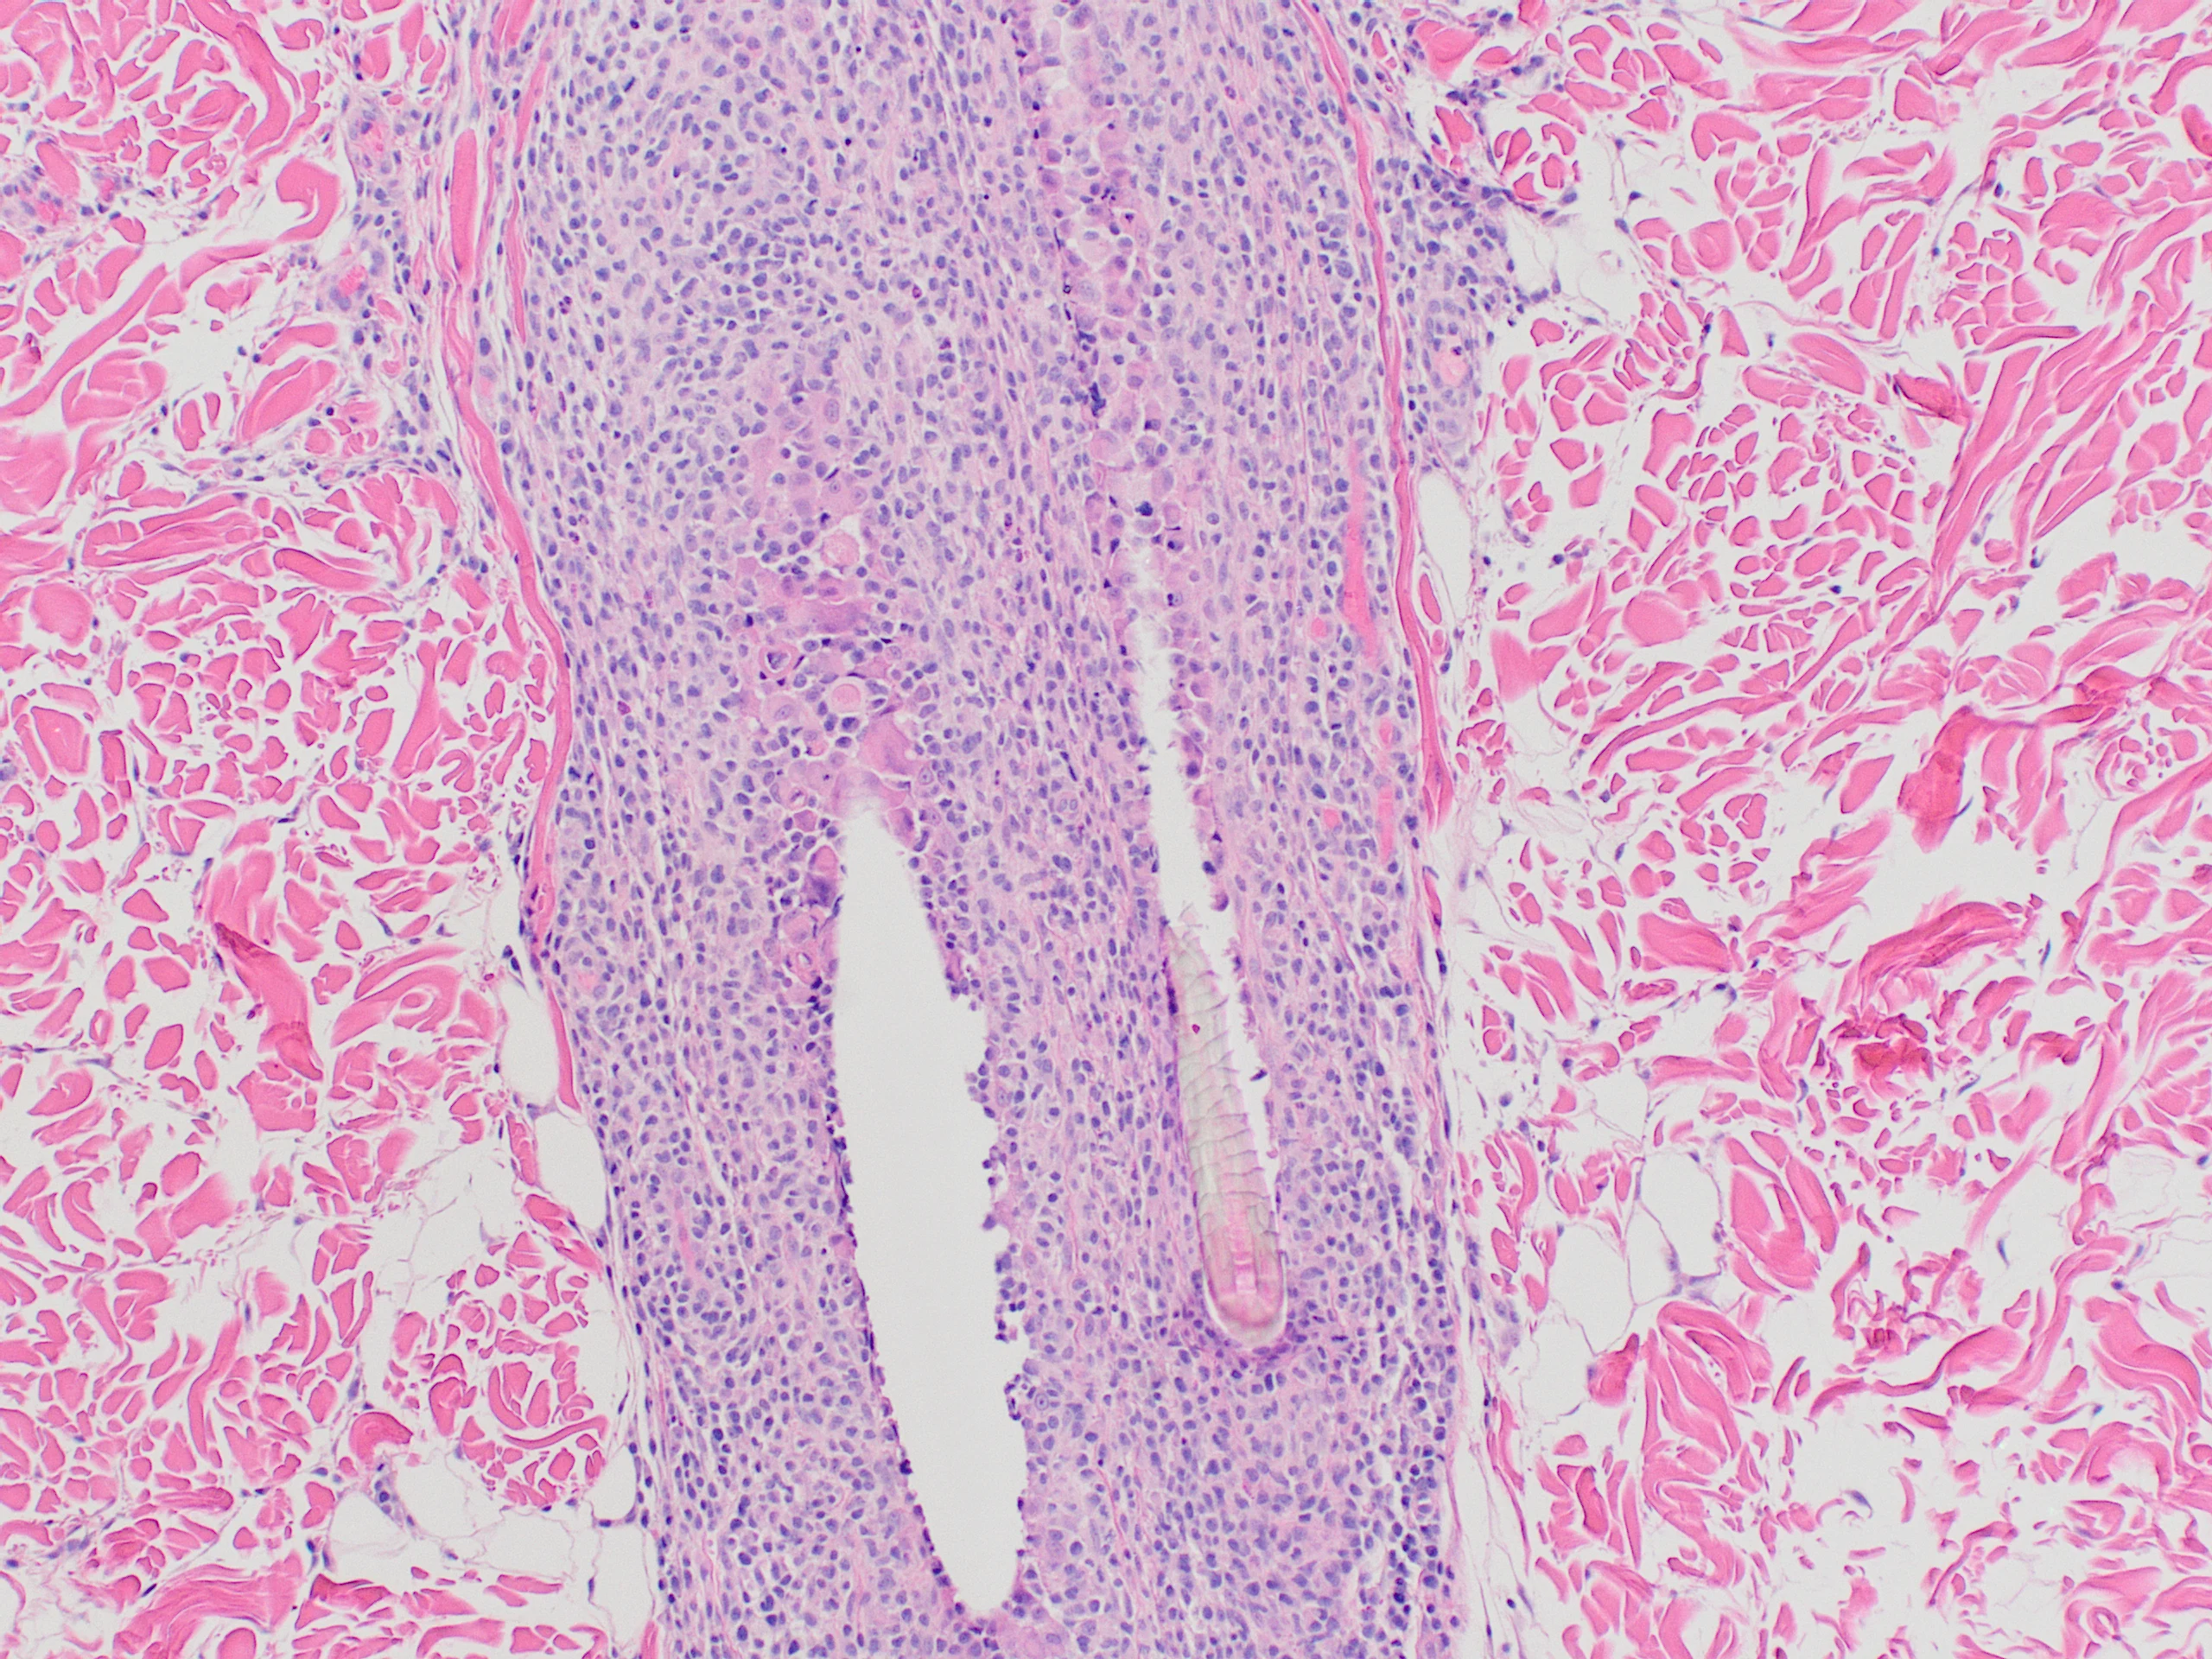

Inflammation is characterized by infiltration of neoplastic T lymphocytes with a tropism for the epidermal or mucosal epithelium, as well as adnexal structures, especially the follicular wall (Figure 4).7,12 Pautrier’s microabscesses (intraepithelial neoplastic lymphocytes diffusely in the epidermis or in aggregates) may be noted.7 Neoplastic lymphocytes that infiltrate apocrine sweat glands occur in 70% of cases and are considered diagnostic (Figure 5).6,7

Neoplastic lymphocytes infiltrating an apocrine sweat gland. Image courtesy of Dr. Shannon Martinson